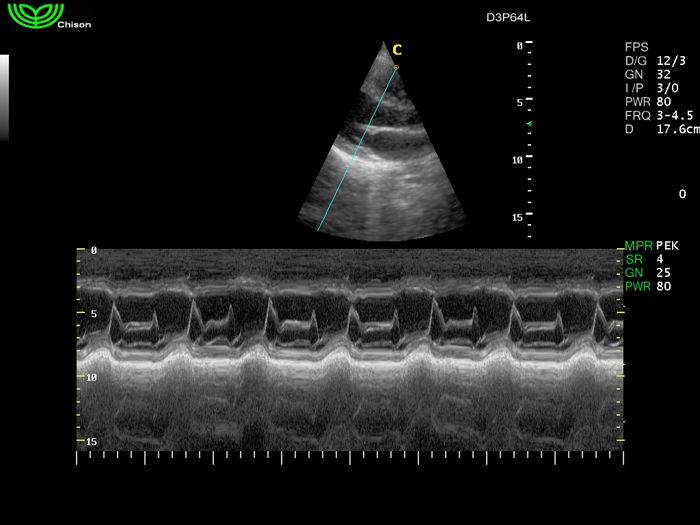

D3P64L 3.0МГц, фазированная решетка.

2.0МГц – 4.4МГц. Применения: кардиология, брюшная полость, акушерство. |